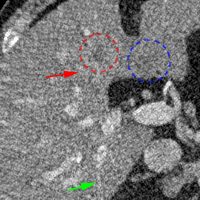

To show the denoising effect of the selected networks, we took two representative slices as shown in Figs. 5 and 7. And Figs. 6 and 8 are the zoomed regions-of-interest (ROIs) marked by the red rectangles in Figs. 5 and 7. All the networks demonstrated certain denoising capabilities. However, CNN-MSE blurred the images and introduced waxy artifacts as expected, which are easily observed in the zoomed ROIs in Figs. 6e and 8e. WGAN-MSE was able to improve the result of CNN-MSE by avoiding over-smooth but minor streak artifacts can still be observed especially compared to CNN-VGG and WGAN-VGG. Meanwhile, using WGAN or GAN alone generated stronger noise (Figs. 6g and 8g) than the other networks enhanced a few white structures in the WGAN/GAN generated images, which are originated from the low dose streak artifact in LDCT images, while on the contrary the CNN-VGG and WGAN-VGG images are visually more similar to the NDCT images. This is because the VGG loss used in CNN-VGG and WGAN-VGG is computed in a feature space that is trained previously on a very large natural image dataset [48]. By using VGG loss, we transferred the knowledge of human perception that is embedded in VGG network to CT image quality evaluation. The performance of using WGAN or GAN alone is not acceptable because it only maps the data distribution from LDCT to NDCT but does not guarantee the image content correspondence. As for the lesion detection in these two slices, all the networks enhance the lesion visibility compared to the original noisy low dose FBP images as noise is reduced by the different approaches.

As for iterative reconstruction technique, the reconstruction results depend greatly on the choices of the regularization parameters. The implemented dictionary learning reconstruction (DictRecon) result gave the most aggressive noise reduction effect compared to the network outputs as a result of strong regularization. However, it over-smoothed some fine structures. For example, in Fig. 8, the vessel pointed by the green arrow was smeared out while it is easily identifiable in NDCT as well as WGAN-VGG images. Yet, as an iterative reconstruction method, DictRecon has its advantage over post-processing method. As pointed by the red arrow in Fig 8, there is a bright spot which can be seen in DictRecon and NDCT images, but is not observable in LDCT and network processed images. Since the WGAN-VGG image is generated from LDCT image, in which this bright spot is not easily observed, it is reasonable that we do not see the bright spot in the images processed by neural networks. In other words, we do not want the network to generate structure that does not exist in the original images. In short, the proposed WGAN-VGG network is a post-processing method and information that is lost during the FBP reconstruction cannot easily be recovered, which is one limitation for all the post-processing methods. On the other hand, as an iterative reconstruction method, DictRecon algorithm generates images from raw data, which has more information than the post-processing methods.